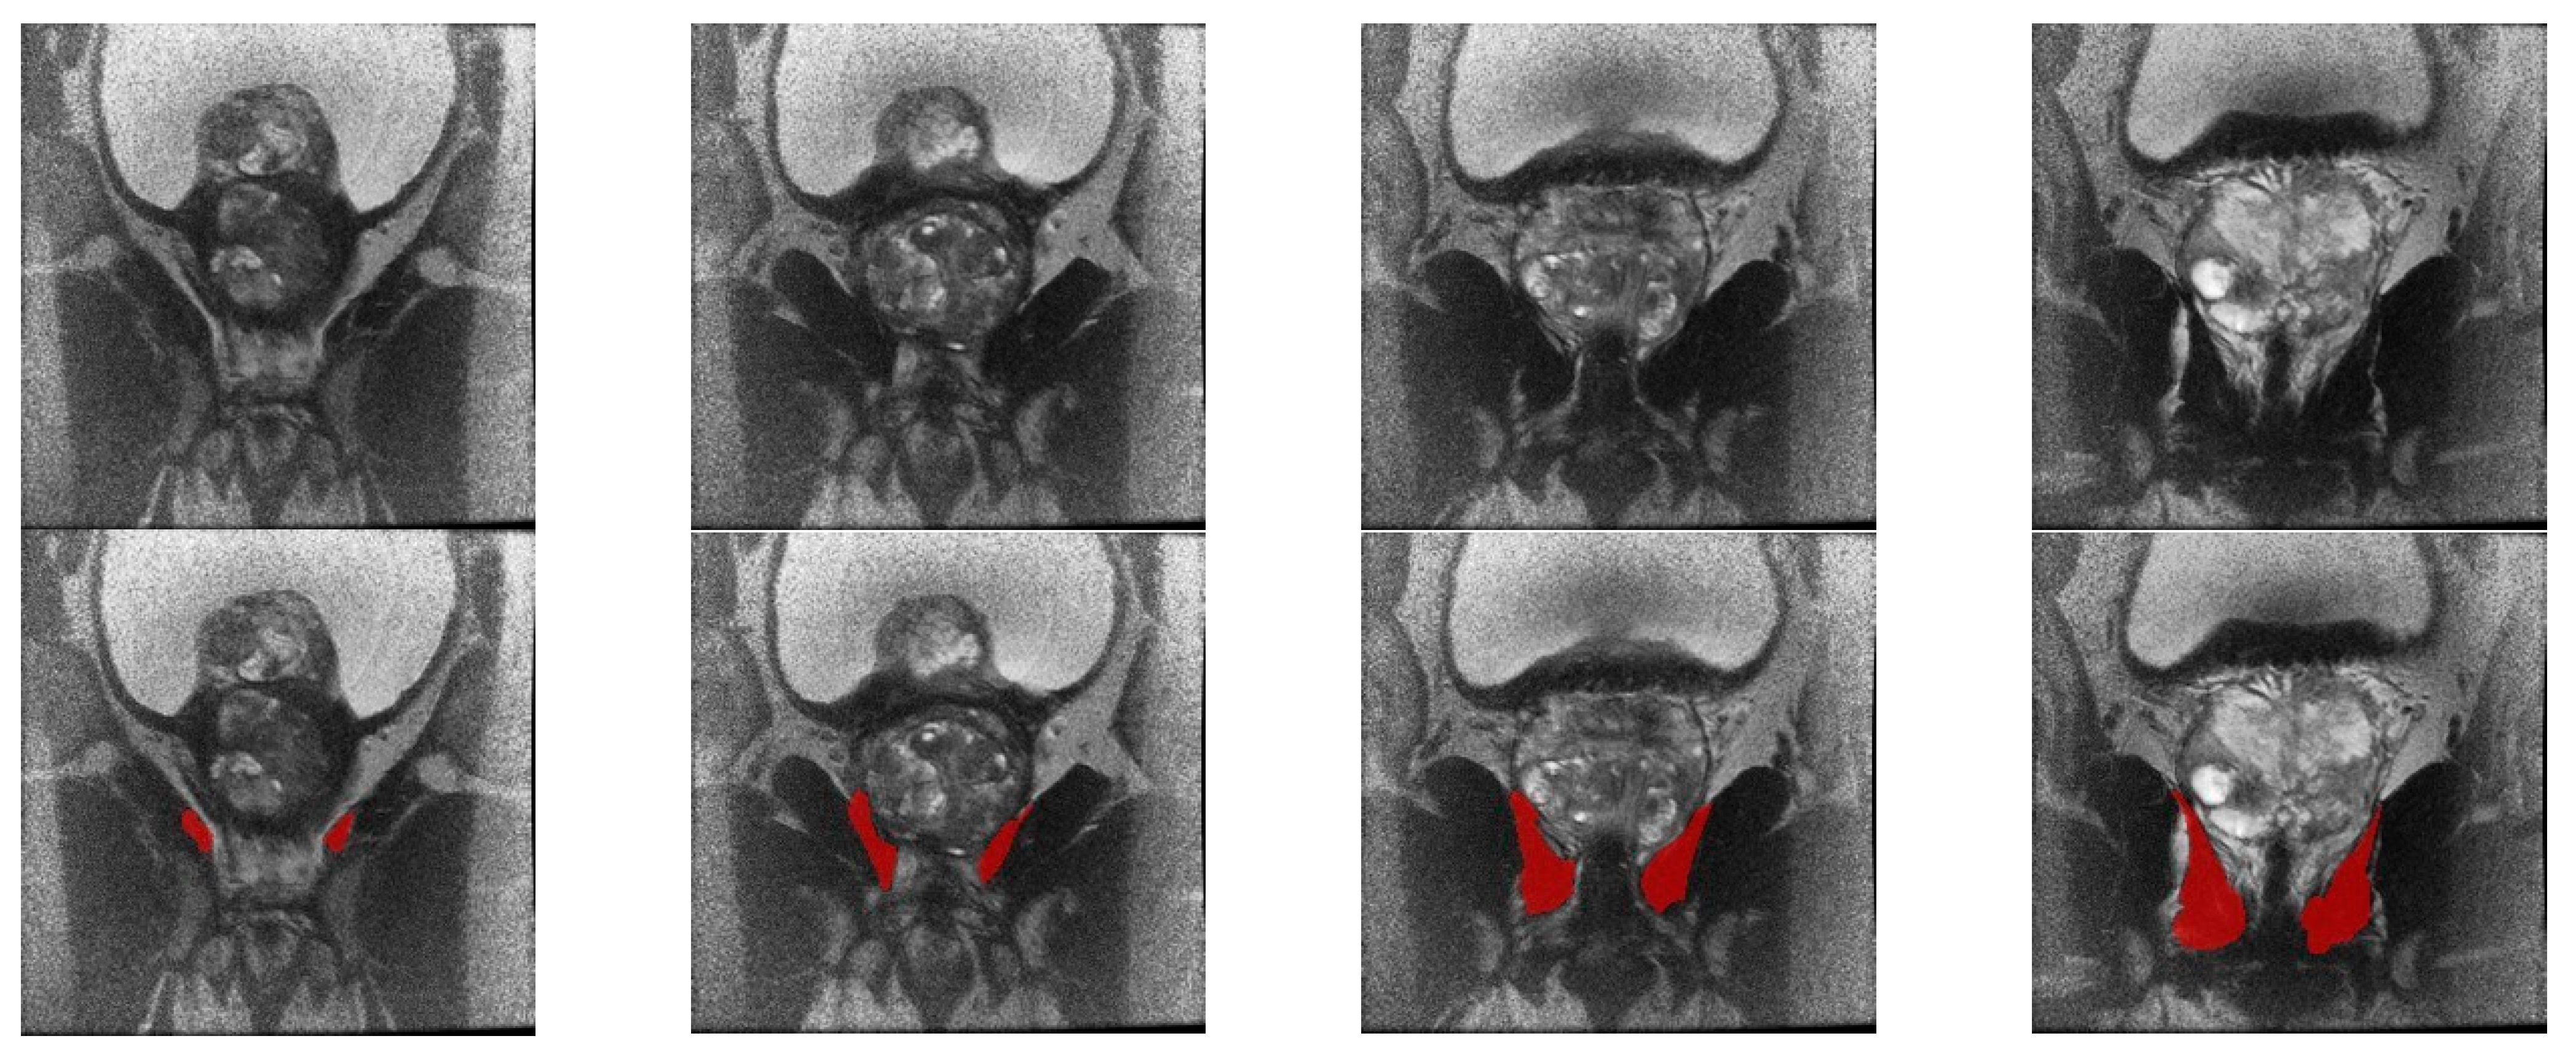

2.2. Image Acquisition and Preprocessing

2.4. Feature Extraction